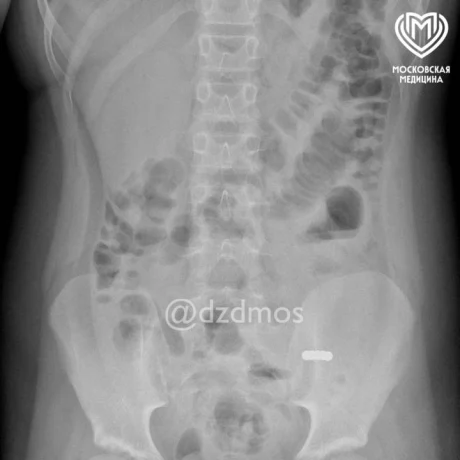

По словам представителей ведомства, девочка пожаловалась родителям на рвоту и жидкий стул. Доктора сделали ей рентген и обнаружили мелкие инородные предметы. Оказалось, что шарики попали в разные петли и сдавили их между собой собственным притяжением друг к другу, из-за чего в кишке образовались «дырки».

Фото: пресс-служба Департамента здравоохранения Москвы